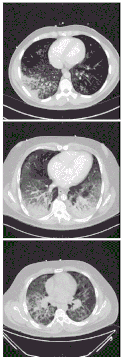

Хвороба вейперів[1], також «Пошкодження легень, пов'язане з вейпінгом», VAPI, EVAPI або E/VAPI[2][3][4] — захворювання легенів, пов'язане з вживанням електронних сигарет, яке може бути тяжким і небезпечним для життя[5]. Початкові симптоми можуть нагадувати пневмонію, але хворі зазвичай не реагують на терапію антибіотиками. Пацієнти зазвичай звертаються за допомогою протягом декількох днів або тижнів після появи симптомів.

Лікарі штату Юта назвали хворобу ліпоїдною пневмонією[10]. CDC відзначили, що симптоми нагадують ГРВІ, а пацієнти після лікування можуть знову зіткнутися з рецидивом захворювання. Після спалаху пандемії коронавірусної хвороби 2019 навесні 2020 року китайські науковці виявили схожість цієї коронавірусної інфекції і хвороби вейперів[11].